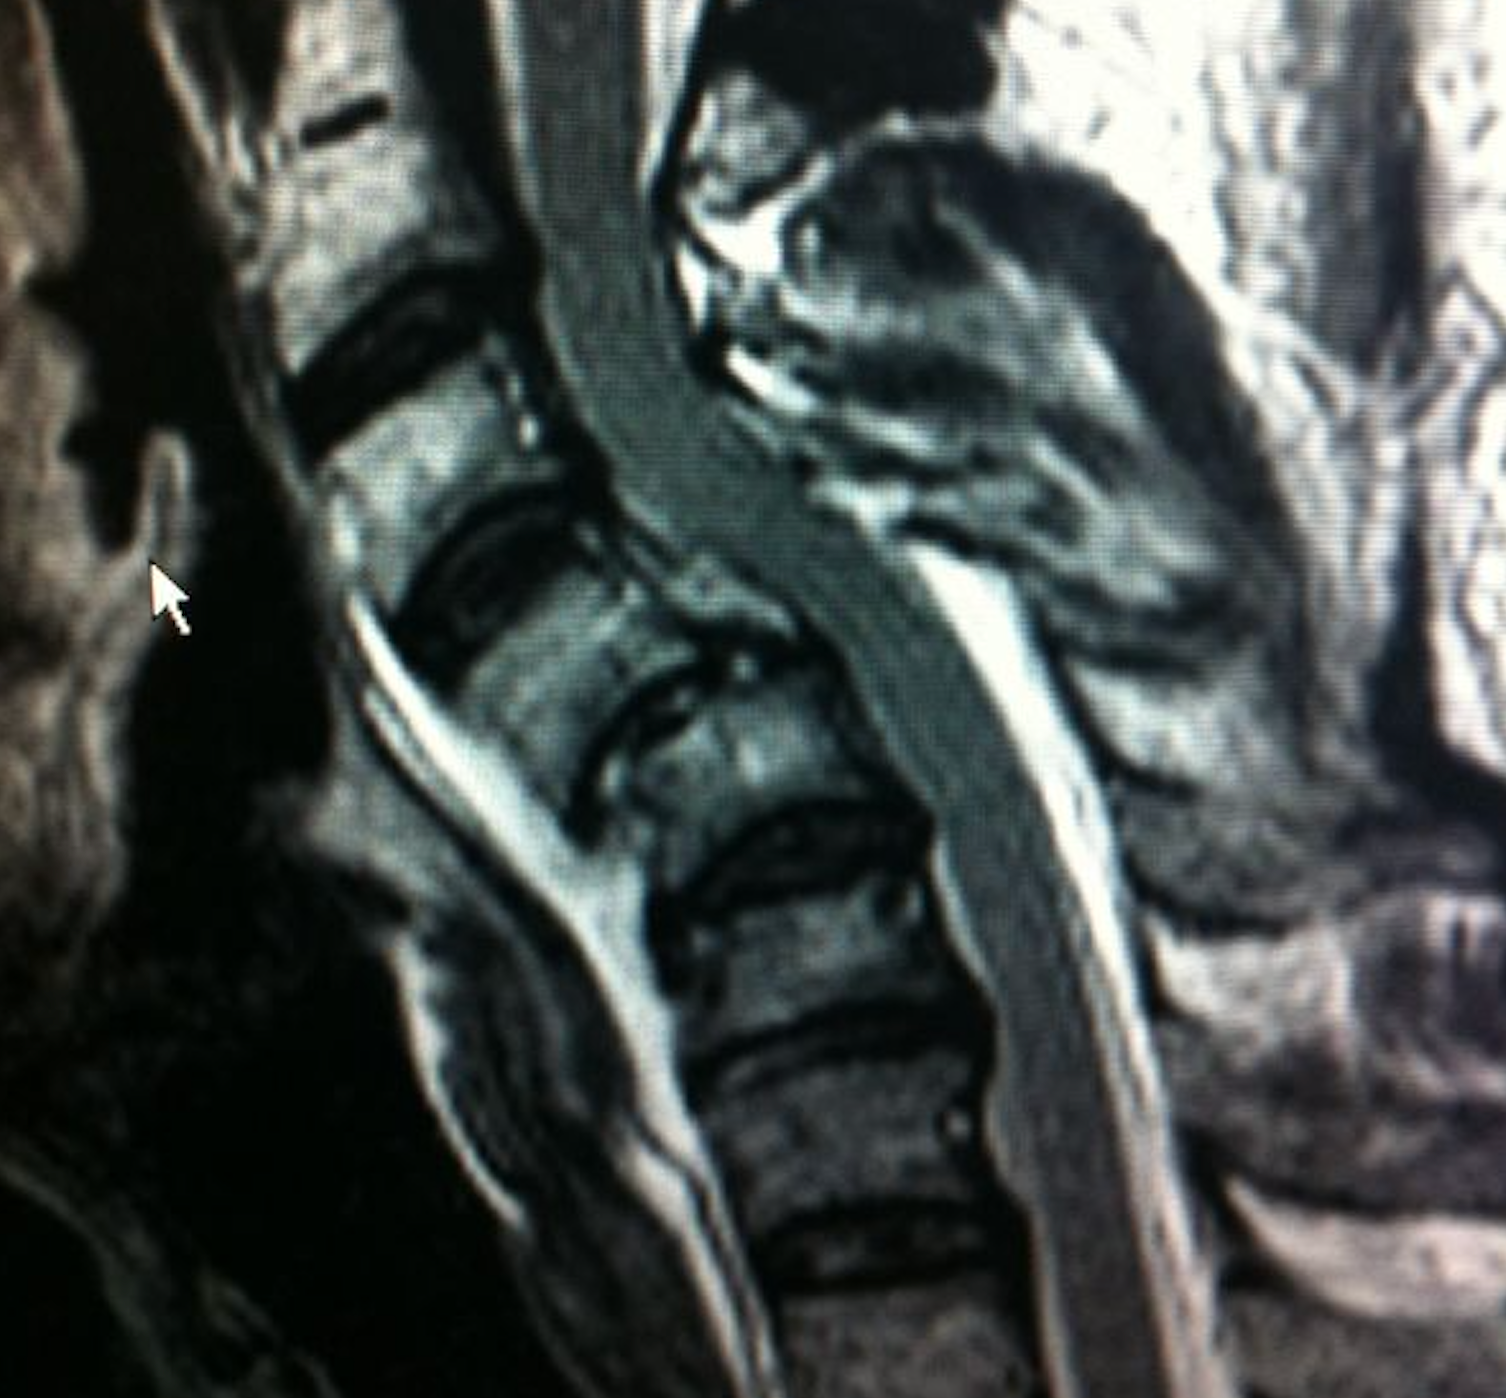

– La RMN proporcionó una mejor visualización del cordón medular, mostrando compresión por la luxación sin signos de sangrado ni edema medular.